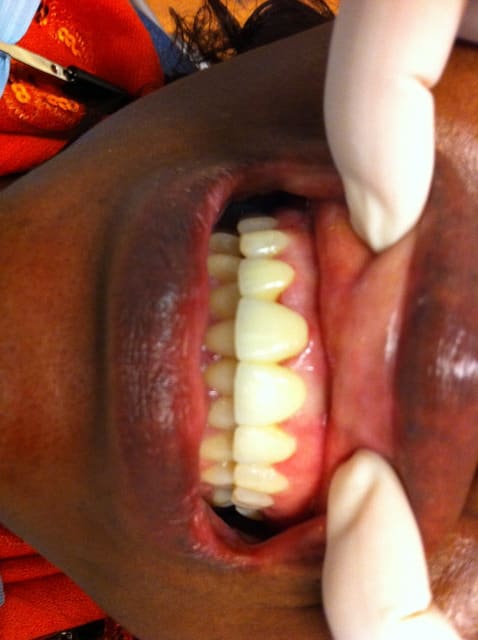

Je déterre mon poste en mettant les photos du cas. Désolé il manque le principal: la photo de l'état initial...

Donc par précaution, j'ai choisi de faire l'endo sur la 22, suite au coiffage direct (même si la dent était asymptotique pour la patiente).

Je n'ai pas osé faire que de l'Emax. J'ai décidé avec le labo de faire une armature Zircone avec de l'Emax pressée dessus.

Il y a les photos du biscuit, du bridge fini le jour de la pose et à 3 semaines.

A vos critiques, merci!